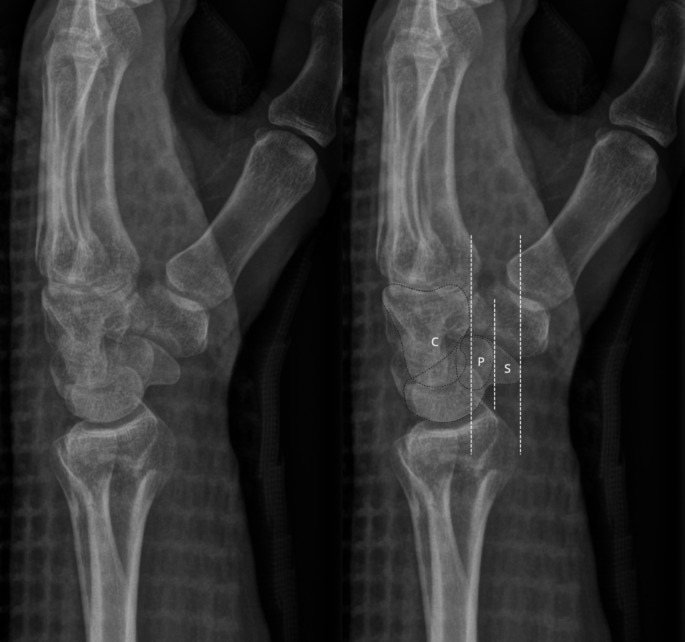

桡骨远端骨折是最常见的骨折类型之一。侧位x线片评估的桡骨远端关节面背侧倾斜常用于确定正确的治疗方法。本报告旨在强调在获得桡骨远端x线片时正确前臂定位的重要性,以及旋前和旋后对桡骨背侧倾斜测量的影响。它提出了一个病例35岁的男性与运动相关的跌倒期间持续的左侧桡骨远端骨折错位。

Distal radius fractures are one of the most prevalent fracture types. Dorsal tilt of the articular surface of the distal radius as assessed on the lateral radiograph is often used in determining the correct treatment method. This report seeks to highlight the importance of correct forearm positioning when obtaining distal radius radiographs, and the effects of pronation and supination on dorsal tilt measurements of the radius. It presents a case of a 35-year-old male with a malaligned left-sided distal radius fracture sustained during a sports-related fall.